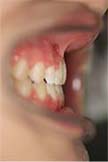

上顎前突 / じょうがくぜんとつ

「出っ歯」と呼ばれるもので、日本人に多い不正咬合です。上の歯が極端に前に突き出る場合や上あごの骨ごと飛び出している場合もあります。

症例名

受け口

治療前

治療後

| 主訴 | 受け口 |

| 診断名 | 下顎前突型のClass IlI不正咬合 |

| 初診時年齢 | 16歳 |

| 主な治療装置 | マルチブラケット装置 |

| 抜歯部位 | 非抜歯(ただし、下顎第三大臼歯は抜歯) |

| 治療期間 | 2年2か月 |

| 治療費 | 矯正治療基本料:60万円 / 調整料 3,000~5,000円×29回 |

| リスク・副作用 | マルチブラケット装置による治療は、口腔を清潔に保たないと、虫歯、歯肉炎、歯周病になるリスクがあり、口腔内の刷掃や治療協力が必要です。このような症例では、下顎歯列の後方移動のために、顎間ゴムの使用が必要です。顎間ゴムの使用が不足すると、治療期間が延長するだけでなく、矯正単独治療から外科矯正治療へと変更する可能性があります。 |